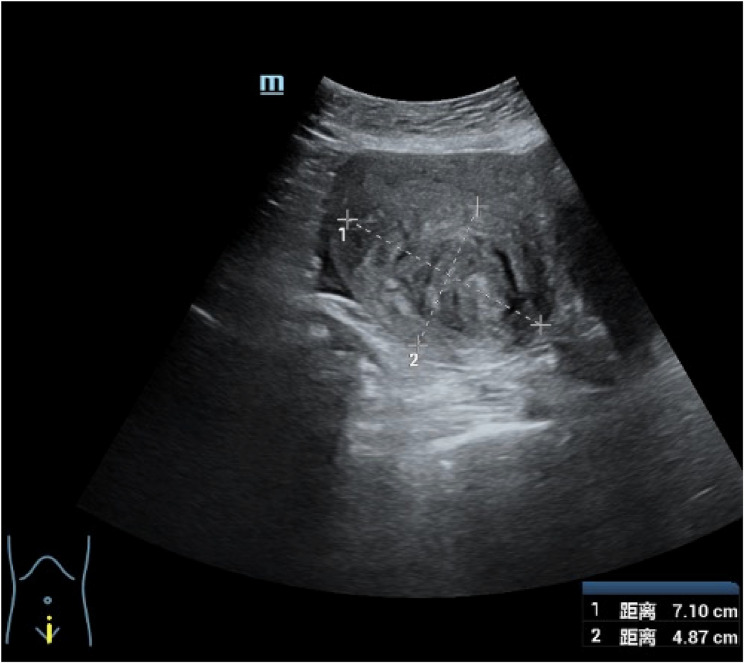

Results: The patient underwent laparoscopic total hysterectomy and bilateral salpingectomy at our hospital more than one year prior because of adenomyosis. No pharmacological treatment was provided postsurgery. One year later, the patient presented with right lumbar discomfort. Imaging revealed hydronephrosis of the right kidney and dilation of the right ureter, leading to a diagnosis of right ureteral endometriosis. Laparoscopic excision of the ureteral endometriotic lesion was performed. Pathology confirmed right ureteral endometriosis with glandular cystic expansion. Postsurgery, the patient was treated with gonadotropin-releasing hormone agonist (GnRH-a) therapy (3.6 mg of goserelin via subcutaneous injection every 28 days for a total of six cycles). Treatment is ongoing. Follow-up ultrasound revealed no abnormalities in the kidneys or ureters, and no recurrence was observed during the five months of follow-up.